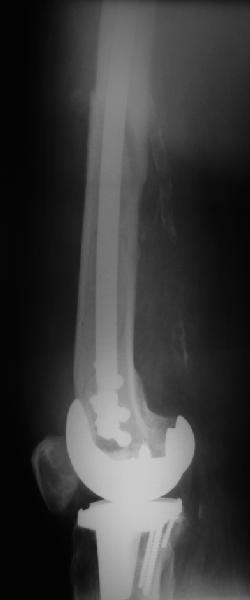

Уважаемые коллеги! 5.08.11 синтез бедренной кости пластиной LCP для дистального бедра.

Прошу совета. П-ка, 59 лет, автодорожная травма, перелом винтообразный н/3 левой бедренной кости. Планировалась закрытая репозиция и малоинвазивный доступ. по ходу операции пришлось немного открыть зону перелома для репозиции. Под контролем ЭОП вроде на столе смещение небольшое было и по оси терпимо. Сделали рентген контроль и получили вот картину. Еще обломилась головка кортикального винта. Синтез то стабильный. Только смещение не только не устранили, но кажется еще чуть больше стало (не могу) первичный снимок сделать). Склонен к ресинтезу и исправлению смещения из расширенного доступа. Как лучше выполнить репозицию? Какие можно использовать приемы репозиции? Спасибо.

конечно реостеосинтез, у Вас нижнии шуруп в линии перелома.

тип 32А1 - межфрагментарная компрессия стягивающим винтом + нейтрализующая пластина(если говорить о накостном остеосинтезе, кроме того пластинку бы подлинее этак на см 5). Ну а лучше - гвоздь с блокированием - закрыто, стабильно, с нагрузкой в послеоперационном периоде.

Коллега,для адекватной оценки перелома необходимо предоставлять предоперационные и послеоперационные снимки в двух проекциях. Насколько возможно судить по маленькой картинке прямой проекции, на первый взгляд тут простой винтообразный перелом 32-А1. В таком случае самый стабильный вариант накостного остеосинтеза - это стягивающий винт перепендикулярно линии перелома и нейтрализирующая пластина. Особых показаний к малоинвазивному мостовидному остеосинтезу нет, т.к. при нем ниже стабильность фиксации, и все микродвижения сконтрентрируются в сравнительно небольшой зоне перелома, что приведет к большим смещающим силам. Однако, если присмотрется, на снимке видно что линия перелома продолжается до начала медиального мыщелка, поэтому скорее всего это клиновидным перелом со спиральным клином 32-В1. В таких случаях возможно выполнение мостовидного синтеза, однако в данном случае дистальная часть клина не смещена относительно дистального конца бедренной кости, таким образом, мне кажется, биомеханически ситуация представляет собой среднее между А1 и чистым В1. Смещающие усилия концентрируются в проксимальной части перелома, тогда как в дистальной несмещенной части они минимальны, в т.ч. из-за интактной надкостницы. Поэтому в данном конкретном случае, при невозможности выполнения интрамедуллярного блокирующего остеосинтеза, я бы выполнил остеосинтез с двумя стягивающими винтами (с рассверливанием ближнего кортикала сверлом большего диаметра) и нейтрализирующего остеосинтеза пластиной. Причем пластина могла бы быть даже обычная.

На представленных снимках, репозиции нет, есть вальгус. Полагаю фиксация не стабильна. Перелом может и срастется, но это будет долго и без нагрузки. Если бы была использована обычная пластина, можно было бы попробовать малоинвазивно подтянуть дистальный отломок и зафиксиривовать парой винтов. Однако примененные блокирующие винты не позволят этого сделать. Как вариант, возможно открытся снизу удалить винты, сделать небольшой доступ в зоне перелома (или попробовать закрыто) ввести 1-2 винта для фиксации клина, и перепровести блокирующие дистальные винты. В любом случае, стабильность при любом из этих вариантов будет заведомо ниже чем при стягивающих винтах + нейтрализирующей пластине. Удачи.

Для принятия решения в данном случае желательно переделать прямую проекцию на длинной кассете с захватом коленного сустава - четче оценить оси, остаточные и качество фиксации; однако и имеющийся снимок не вызывает ощущения катастрофы - вполне неплохо должно срастаться.